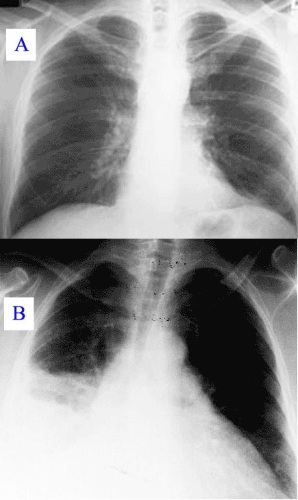

Рентгенография легких – наиболее эффективный метод диагностики, стоимость которого не превышает 300 руб.

Проводится в любом учреждении и помогает выявить локализацию очага поражения. Благодаря снимкам специалист может оценить степень поражения тканей.

Благодаря комплексной диагностике врач выявляет стадию и форму болезни, что помогает назначить наиболее адекватную терапию.